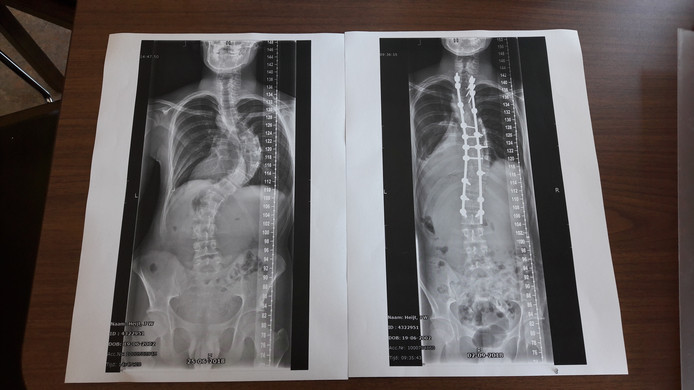

,,Hoe gaan we het fixen?", Jetze kijkt de orthopeed vragend aan. Die meldt dat een operatie niet voor de hand ligt. ,,Daar wordt je rug zo stijf van." Maar om het zeker te weten, stuurt hij ons door naar de Sint Maartenskliniek in Boxmeer, daar werken orthopeden die zijn gespecialiseerd in het behandelen van scoliose. Daar zitten we dan. In het Bravis Ziekenhuis in Bergen op Zoom, precies een jaar geleden. Bij onze zoon is officieel vastgesteld dat hij scoliose heeft, een kromming in de ruggengraat. Niet zomaar een kromming, hij heeft een bocht van meer dan 60 graden. Dan sta je behoorlijk scheef. Afgelopen week is zijn wervelkolom rechtgezet met behulp van stalen schroeven en pinnen. Een chirurgisch meesterwerk als je het ons vraagt. Het resultaat: Jetze staat weer in het lood en is zelfs 6 centimeter langer.

De röntgenfoto die we afgelopen najaar onder ogen krijgen, is confronterend. Een wervelkolom met een bocht, een soort omgedraaide C aan de rechterkant. Tijdens een mooie nazomerdag liepen we in 2017 over het strand toen Jetze bukte. Toen viel me voor het eerst de kromming in zijn rug op. U denkt vast en zeker dat ik dat eerder had moeten zien, maar dat is dus niet zo. Ik zie hem vaker in zijn blote bast voorbij komen. Dat de kromming ook 'aan de buitenkant' zichtbaar is, is heel recent. De scoliose heeft een groeispurt ingezet, we hebben het nooit eerder bij hem gezien en Jetze heeft ook nooit eerder klachten gehad. Ook nu niet trouwens. Het blijft heel opmerkelijk. Zo heb je nog nooit van een scoliose gehoord, zo weet je dat Jetze nog heel wat te wachten staat.

De mededeling zorgt voor een gevoel van zowel opluchting als ongerustheid. Ik heb gegoogled op scoliose en operatie en de resultaten zien er indrukwekkend uit. Röntgenfoto's van wervelkolommen waarin een soort stalen pinnen en schroeven zijn verwerkt om de boel weer recht te zetten. Een zware ingreep voor een jongen van 16. Aan de andere kant; als er niets wordt gedaan, komt zijn rechterlong in de verdrukking en krijgt hij hoe dan ook rugpijn door de kromme houding. Ik lees veel positieve ervaringen van andere jongeren die dezelfde operatie hebben ondergaan, die verhalen had ik even nodig.

Dan het grote herstel. De eerste dagen is Jetze erg misselijk van de medicijnen, maar als de morfinepomp wordt afgesloten, is dat ver over. Uiteraard heeft hij rugpijn, maar het is te doen. We zijn onder de indruk van de röntgenfoto van zijn ruggenwervel voor en na de operatie. De pinnen hebben hun werk gedaan, hij staat recht, de bocht is er zo goed als uit. We vinden het een wonder van de moderne geneeskunde. Chapeau voor het zorgteam van de Sint Maartenskliniek. Als Jetze voor het eerst wat wiebelig gaat staan, zien we het resultaat van het 'rechttrekken': hij is een stuk groter. Als hij wordt gemeten, blijkt dat er 6 cm bij is gekomen; van 1.82 naar 1.88 meter. Met stip de langste van de familie.